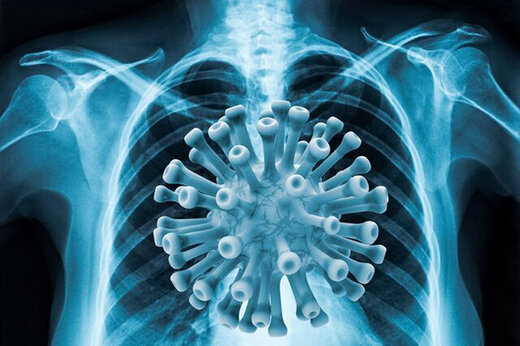

واکسن نزن ها؛ ۹۰ درصد بستریها / آمار بستری واکسن نزنها و کودکان هشدارآمیز شد

اینکه ۹۰ درصد بستریشدگان مبتلا به امیکرون، واکسننزدهها هستند دوباره ثابت میکند که هیچ راهی بهتر از واکسینهشدن برای مقابله با کرونای منحوس وجود ندارد و تعلل در تزریق دوزهای اول، دوم و سوم، میتواند اوضاعمان را بحرانیتر کند.

دیدارنیوز ـ دیگر همه فهمیدهایم که سویه امیکرون، نه تنها کمخطر نیست بلکه قدرت کشندگی هم دارد و بعد از قتلعامی که در برخی کشورها به راه انداخته، حالا آمار فوتیهای روزانه ما را هم دوباره سهرقمی کرده است. دیروز ۱۱۴ هموطن دیگرمان را به دلیل کرونا از دست دادیم و به نظر میرسد روزهای تلختری هم پیش رو داشته باشیم، با این حال هنوز برخی از مردم حتی برای تزریق دوز اول واکسن هم مراجعه نکردهاند.

با وجود همه تاکیدات، در کشور ما هنوز برخیها واکسنگریزند و جان خود و دیگران را به بازی گرفتهاند. طبق آمار، تعداد تزریقکنندگان دوز اول به ۶۱ میلیون رسیده و این یعنی هنوز چندین میلیون نفر حتی دوز اول را هم تزریق نکردهاند. آمار تزریقکنندگان دوز دوم هم به ۵۴ میلیون رسیده و باید منتظر افزایش تعداد آن بود.

سرعت کند دوز سومی ها

وجه اشتراک ۹۰ درصد بستریهای جدید

آمار وزارت بهداشت را هم بخوانیم تا بدانیم واکسن نزدن چه بلایی بر سرمان آورده است: «۹۰ درصد افرادی که در این سویه بستری میشوند، واکسن تزریق نکردهاند و علاوه بر آن، کاهش رعایت پروتکلهای بهداشتی و اجتماعات خانوادگی در شیوع امیکرون در جامعه تاثیر زیادی داشته است».

کودکان ۲۰ درصد بستریها

خبرهای نگرانکننده امیکرونی تمامی ندارد و باید به این نکته هم اشاره کنیم که طبق اعلام وزارت بهداشت ابتلای کودکان به اُمیکرون بسیار قابل توجه است و حداقل ۲۰ درصد موارد بستری تنفسی اخیر، از بین کودکان هستند. مصداق تلخش هم اینکه، رئیس بیمارستان کودکان ابوذر اهواز، از بستری شدن ۲۷۰ کودک مبتلا به کرونا و پرشدن تختهای این بیمارستان خبر داد.

واکسیناسیون زیر ۱۲ سالهها را جدی بگیرید

با توجه به این شرایط وخیم، شک نکنید که واکسینهکردن زیر ۱۲ سالهها یک ضرورت است و خانوادهها نباید از آن غفلت کنند. خوشبختانه واکسیناسیون کودکان ۹ تا ۱۲ سال در حال انجام است ضمن آنکه واکسیناسیون ۵ تا ۹ سالهها هم از امروز امکانپذیر شد. در کنار اهمیت بالای واکسیناسیون، رعایت دستورالعملهای پیشگیرانه هم یک بخش مهم ماجراست که ما حتی در پیک ششم در آن لنگ میزنیم؛ هم مردم در این رعایتکردنها کوتاهی میکنند و هم نهادهای مسئول تقریبا بیخیال نظارتها و مداخلات موثر شدهاند. دکتر «حمید سوری»، رئیس کارگروه بهداشت و پیشگیری قرارگاه عملیاتی ستاد ملی مقابله با کرونا، دراینباره میگوید:

منتظر شکسته شدن رکورد باشیم

دکتر سوری یک پیشبینی هم درباره روزهای پیش رو ارائه میکند: «سرعت شیوع سویه امیکرون خیلی زیاد است و احتمالا ما در طول ۴ تا ۶ هفته پیک بیماری، به بیشترین آمار مبتلایان کرونا طی دوسال اخیر خواهیم رسید». البته او ابراز امیدواری میکند که با توجه به تجربه جهانی و قدرت کمتر این سویه در افزایش آمار بستری و مرگ، به وضعیتی مشابه موج دلتا نرسیم.